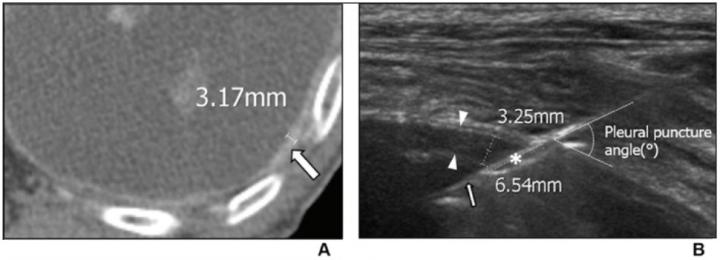

image: Enhanced axial CT (A) shows diffuse pleural thickening (arrow) with a maximum thickness of 3.17 mm. US image for the corresponding lesion on CT (B) shows diffuse pleural thickening (arrowheads) with a maximum thickness of 3.25 mm. The needle pathway length, measured as the needle length through the pleural lesion, was 6.54 mm (asterisk). Pleural puncture angle (exact value not indicated) is depicted as the angle between the outer line of the pleura and the biopsy needle (thin arrow).

82-Year-Old Man Diagnosed With Tuberculous Pleurisy on US-Guided PCPNB (see image)